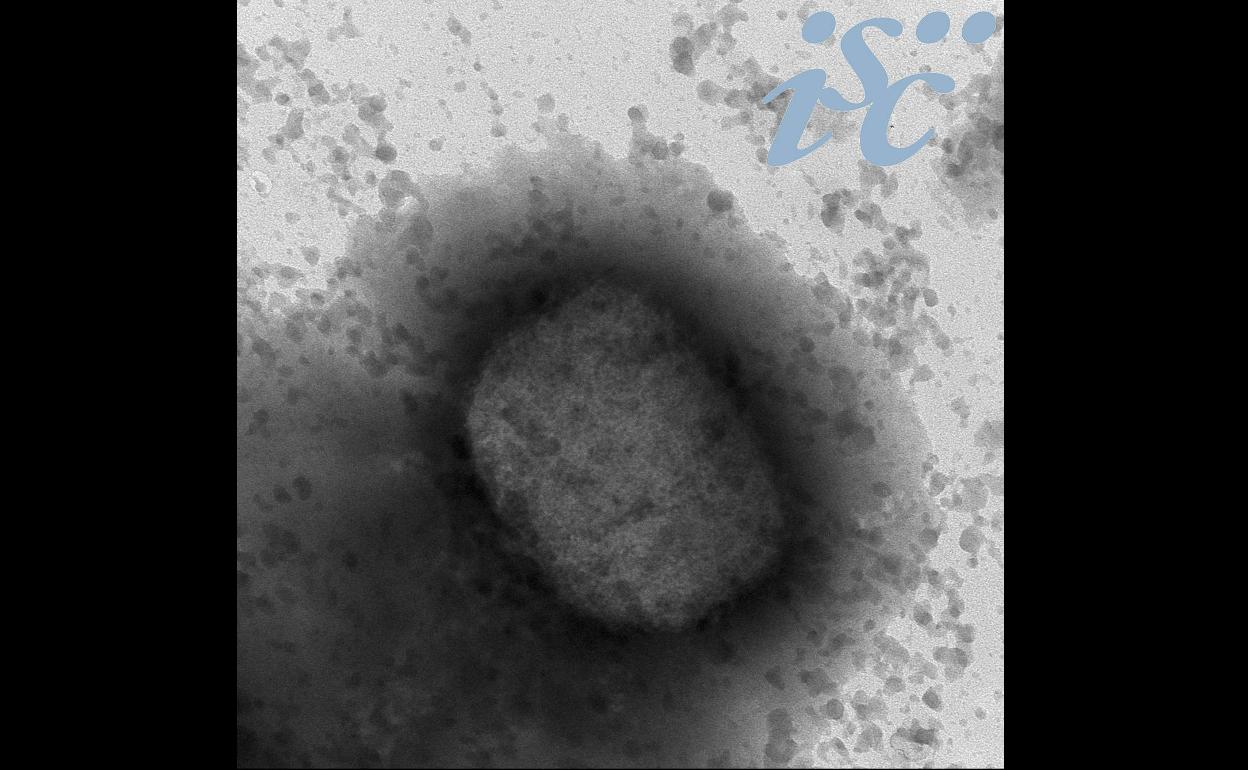

Virus de la viruela del mono por microscopía electrónica, facilitada por el Instituto de Salud Carlos III (ISCIII).

Castilla y León investiga dos casos por sospecha de viruela del mono

La Junta de Castilla y León, a través de la Dirección General de Salud Pública, ha activado el protocolo de actuación, epidemiológica y asistencial, ante dos casos sospechosos de infección por viruela del mono en dos provincias de la comunidad, pero sin especificar cuáles son estas.